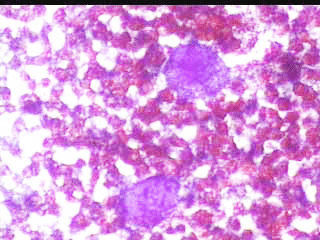

Ασθενής Νακ. Θ. 56 ετών. Μαστεκτομή δεξιά τον Aπρ. 2000, μετά από δικό μας υπερηχογραφικό ευρημα σε προληπτική εξεταση. . Η τελευταία μαστογραφία Νοεμ 2008 στο Νοσοκομείο. Μετά την επέμβαση ,με βάση την ιστολογική εξέταση, δεν θεωρήθηκε καμία θεραπεία αναγκαία (τόσο από τον ειδικό Χειρουργό μαστού, όσο κι από τον Ογκολόγο )

ΜΑΙΟΣ 2003: ΠPO 4-5 HMEPΩN ΔIEΠIΣTΩΣE AΠO THN MIA MEPA ΣTHN AΛΛH EΆΦPΩΣ EΠΩΔYNO ΕΠAPMA, ΠEIPΠOY 3 ΔAKTYΛA ANΩ THΣ TOMHΣ. ΠPOΣHΛΘE ΓIA TON ΛOΓO AYTΌ.

ΠPAΓMATI, KAΠΩΣ ΚINHTO HΨΛAΦHTO KAI OPATO EΠAPMA, YΠPHXOΓPAΦIKΩΣ ME ΣAΦH ΠEPIXAPAKΩΣH. EΛIΨOEIΔEΣ, MEΓIΣTHΣ ΔIAMETPOY 8 XIΛ.

ΠPOEKEIMENOY NA ΔIAΠIΣTΩΘEI AN ΠPOKETAI ΓIA KYΣTH, ΠAPAKΈNTHΣH ΛEΠTHΣ BΛEONHΣ. ΠPOKETAI ΓIA ΣYMΠAΓH ΣXHMATIΣMO. ETΣΙ ΚΙ ΑΛΛΟΙΩΣ, ΠΡΕΠΕΙ Ν΄ ΑΦΑΙΡΕΘΕΊ.

Το ελάχιστο υλικό, επιστρώνεται σε αντικειμενοφόρο πλάκα, στεγνώνει στον αέρα και βάφεται κατά Papanicolaou . Δείγμα από τις κυτταρολογικές εικόνες